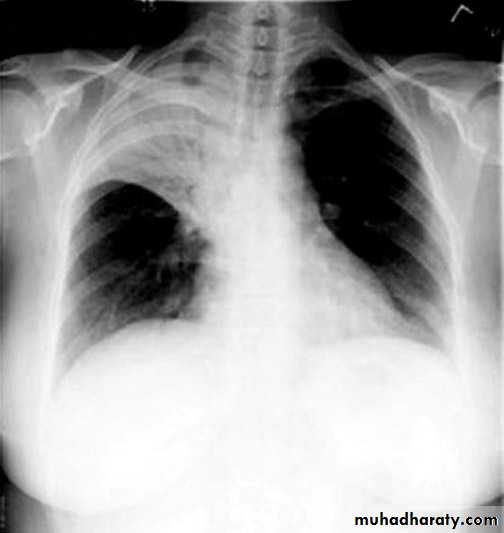

Pleural effusion

50.pleural effusion

51.pleural effusion .